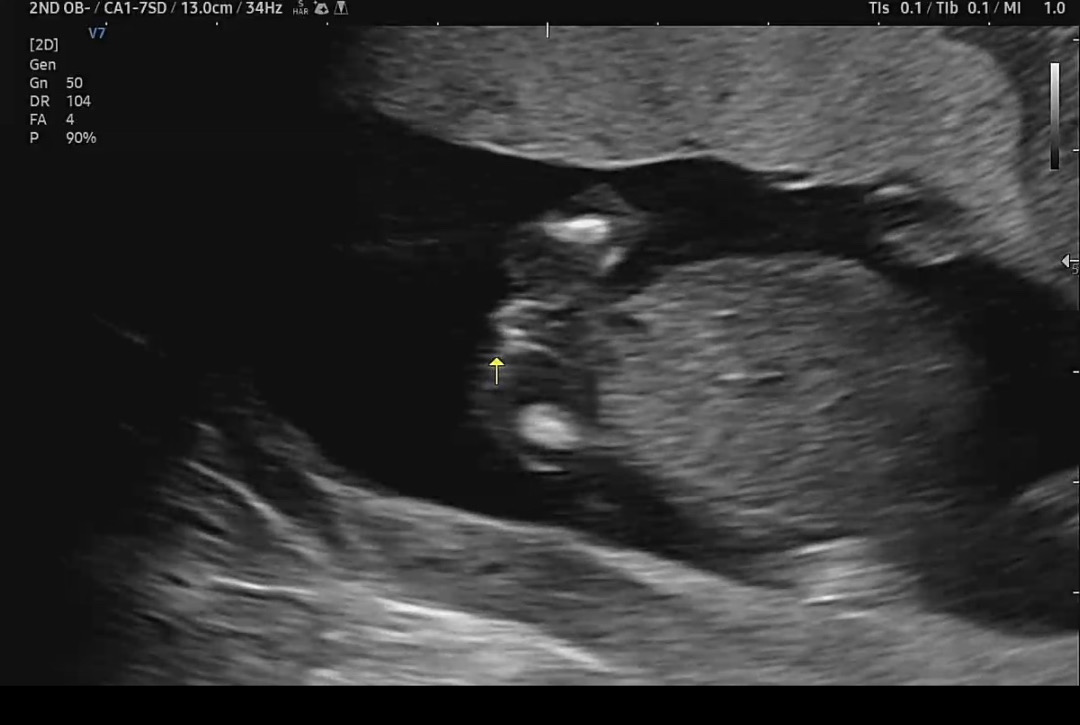

15주3일차 성별이 뭘까요?

안녕하세요! 아직 튀어나온게 안들어간건지 튀어나온건지 넘 궁금한데 고수님들 추측부탁드려요!